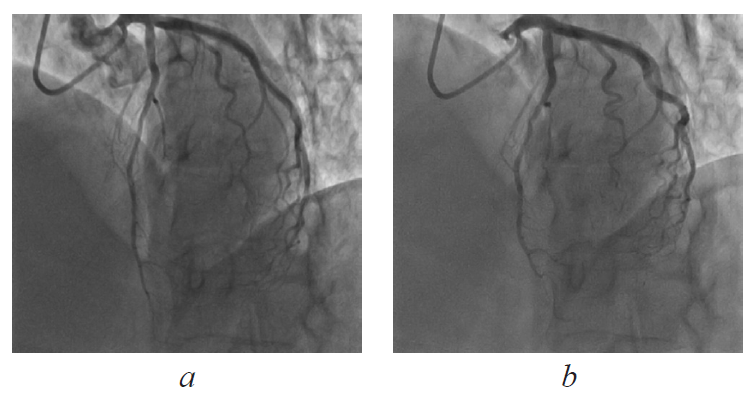

Cardiovascular diseases (CVDs) are the leading cause of mortality among the population. At the core of the progression of the coronary heart disease is the atherosclerosis of the coronary arteries, which is found in majority of patients suffering from angina and in patients with myocardial infarction. However, in some cases, coronary angiography reveals, that patients with the mentioned clinical manifestations have their coronary arteries unchanged. This is treated as syndrome X or microvascular angina. Along with that, development or aggravation of the coronary heart disease may be based on the congenital peculiarities in the coronary arteries location and structure, such as muscular bridges and fistulas of the coronary artery. This is confirmed by a number of studies, which indicate the role of the above mentioned pathologies in the occurrence of angina and myocardial infarction. Nevertheless, there is also the opposite view, which is supported by a number of specialists. According to them, the presence of the mentioned peculiarities in the structure of the coronary channel is deemed as the patient-specific norm. Hence, the issue of the surgical treatment of the patients with the aforementioned coronary arteries anomalies remains controversial. The clinical case report of the patient with the symptoms of angina pectoris, in which the coronary angiography did not reveal the stenosis of the coronaries arteries, but located the myocardial bridge and the coronary fistula. The role of the congenital coronary vessels pathology in the angina pectoris is analyzed. The diagnosis guidelines and the tactics of the conservative and surgical treatment of patients with the above mentioned syndromes are discussed.